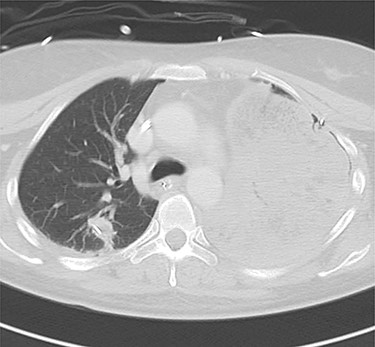

Axial (A) and sagittal (B) computed tomography images few hours after initial emergency operation.

A 38-year-old woman with schizophrenia committed suicide by a self-infliction of sharp force into the chest and abdomen. She presented to our hospital in a critical condition. On arrival in the emergency room (ER), she developed hemorrhagic shock, which leads to an emergent abdominal damage control surgery under general anesthesia. She lost cardiac activity in the operating room during exploratory laparotomy. A left-sided basal thoracostomy, cross-clamping of the descending thoracic aorta, and open cardiac massage were also performed. She received gauze packing at the bleeding point and temporarily close the abdomen and chest wall. After the surgery, she was transferred to the intensive care unit with mechanical ventilation and recovered from hemorrhagic shock. Two days later, a second-look laparotomy was performed. ER doctors verified the hemostasis and closed the patient’s abdomen and chest. On the same day, a chest radiograph revealed pulmonary atelectasis of the left upper lobe (Fig. 1). Computed tomography (CT) revealed alveolar bleeding, pneumonia and atelectasis of the left upper lobe (Fig. 2). Despite antibiotic therapy and repeated endobronchial sputum aspiration, radiologic findings were not improved. On the seventh postoperative day, she was referred to our department for suspected lung abscess. When compared to the chest CT images on the day of initial surgery, pulmonary torsion was suggested (Fig. 3A). The sagittal CT images were reconstructed, and the torsion of the left upper lung lobe was diagnosed (Fig. 3B). Therefore, an emergency left upper lobectomy was performed through a left thoracotomy. Intraoperatively, the left upper lung lobe was rotated clockwise and was hemorrhagically and congestive infarcted. Due to severe pulmonary congestion, it was difficult to obtain the surgical field of view. The pericardial sac was opened and the intrapericardial isolation of the left upper pulmonary vein was performed. To prevent separation of the thrombus and necrotic material in the left upper lobe, we first dissected the left upper pulmonary vein before resolving the torsion and performing the lobectomy. She had a complete pulmonary fissure. Moreover, only one first pulmonary artery branch had ruled the approximately pulmonary arterial flow of her left upper lobe. The left upper lobectomy was performed. The patient made an uneventful recovery.